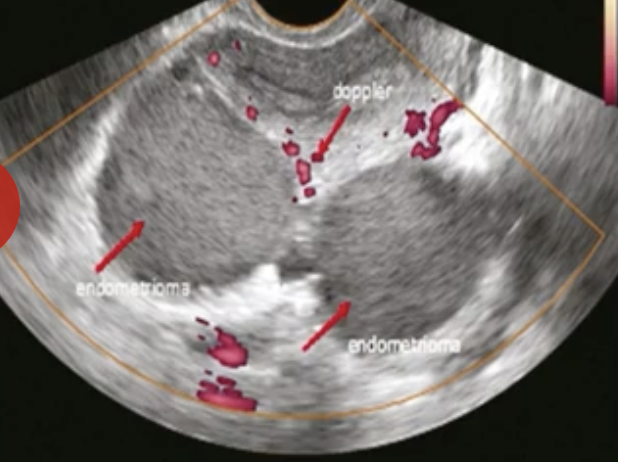

Qual o achado evidenciado na figura?

A

Kissing Ovaries

Observação: É um achado mais comum nas pacientes com endometriose grave